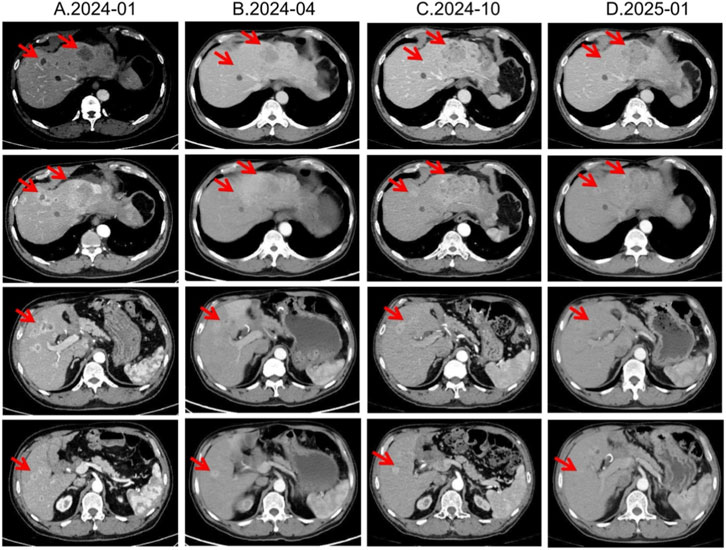

In January 2024, third-line treatment with everolimus 10 mg daily was initiated. Everolimus, an oral mTOR inhibitor, has been shown in RADIANT-3 and RADIANT-4 to significantly delay progression of advanced pNETs (Yao et al., 2016). In April and July 2024, CT scans demonstrated shrinkage of most hepatic lesions, with the treatment response assessed as a partial response (PR). However, owing to multiple small-intestinal ulcers at that time, the everolimus dose was reduced to 5 mg once daily in August 2024. Subsequent CT re-evaluations in October 2024 and January 2025 both showed SD (Figure 4).

CT scan panel showing four columns labeled A.2024-01, B.2024-04, C.2024-10, and D.2025-01. Each column contains four images of abdominal cross-sections with red arrows indicating specific areas. The images show various changes over time, highlighting differences in the liver region.

Figure 4. Lesion changes in patients during third-line everolimus treatment. (A) 2024-01 CT shows: Multiple weakly enhanced nodules in the liver, the largest of which is approximately 4.3 cm × 2.8 cm in size. (B) 2024-04 CT shows: The liver lesions have decreased and shrunk compared with most of the previous lesions. Treatment response evaluation: PR. (C) 2024-10 CT shows: Multiple slightly low-density nodular mass shadows in the liver, especially in the left outer lobe of the liver. Enhanced scans show uneven enhancement. Treatment response evaluation: SD. (D) 2025-01 CT shows: Multiple slightly low-density nodular mass shadows in the liver, especially in the left outer lobe, and enhanced scans show heterogeneous enhancement. Treatment response evaluation: SD.